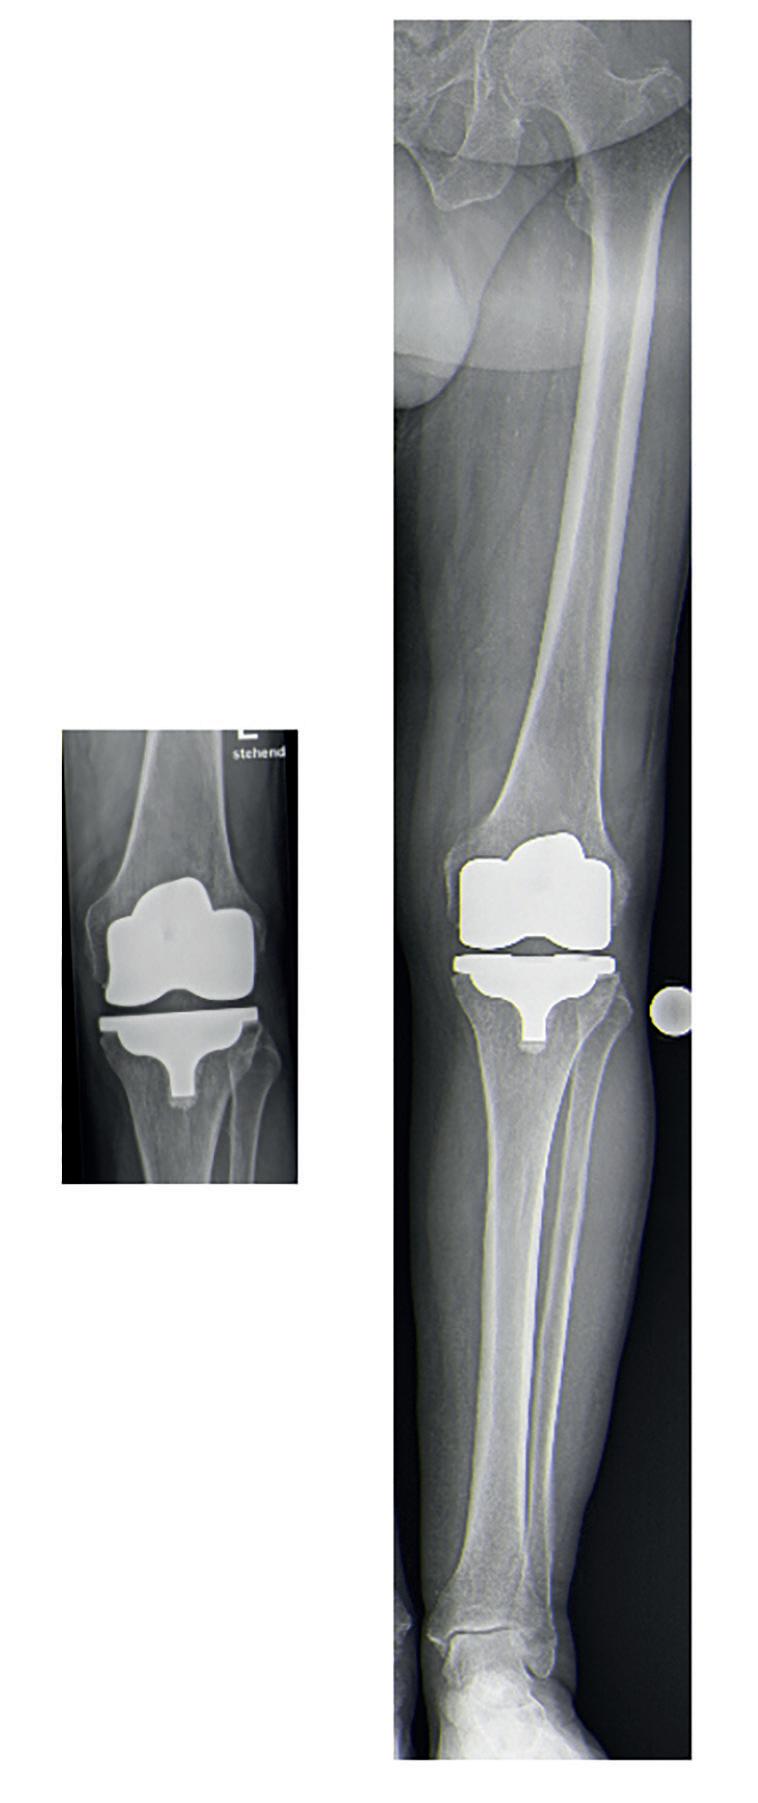

© Prof. Rath

Abbildung 3: Röntgenbilder nach KTEPImplantation (kinematisches Alignment). Links: Aufnahme des Kniegelenkes. Rechts: Ganzbeinstandaufnahme desselben Kniegelenkes.

Postoperatives Röntgenbild

Wichtig ist bei dieser Operationstechnik, auch die niedergelassenen Kolleg:innen in den Behandlungsvorgang einzubeziehen. Sie sollten mit dem Prinzip und der Vorgehensweise vertraut sein. Allein die Beurteilung des postoperativen Röntgenbildes kann ansonsten teilweise für Verwirrung sorgen, da die Gelenklinie hier nicht horizontal erscheint und eine nicht optimale Prothesenorientierung

angenommen werden könnte. Diese Darstellung in kurzen (nicht das ganze Bein betreffenden) Röntgenbildern ist allerdings korrekt. Interessanterweise spiegelt sich die Rationale der Implantationstechnik in der Ganzbeinstandaufnahme wider. Hier zeigt sich die Tibiakomponente und somit auch die Gelenklinie orthograd zum Boden (Abbildung 3).